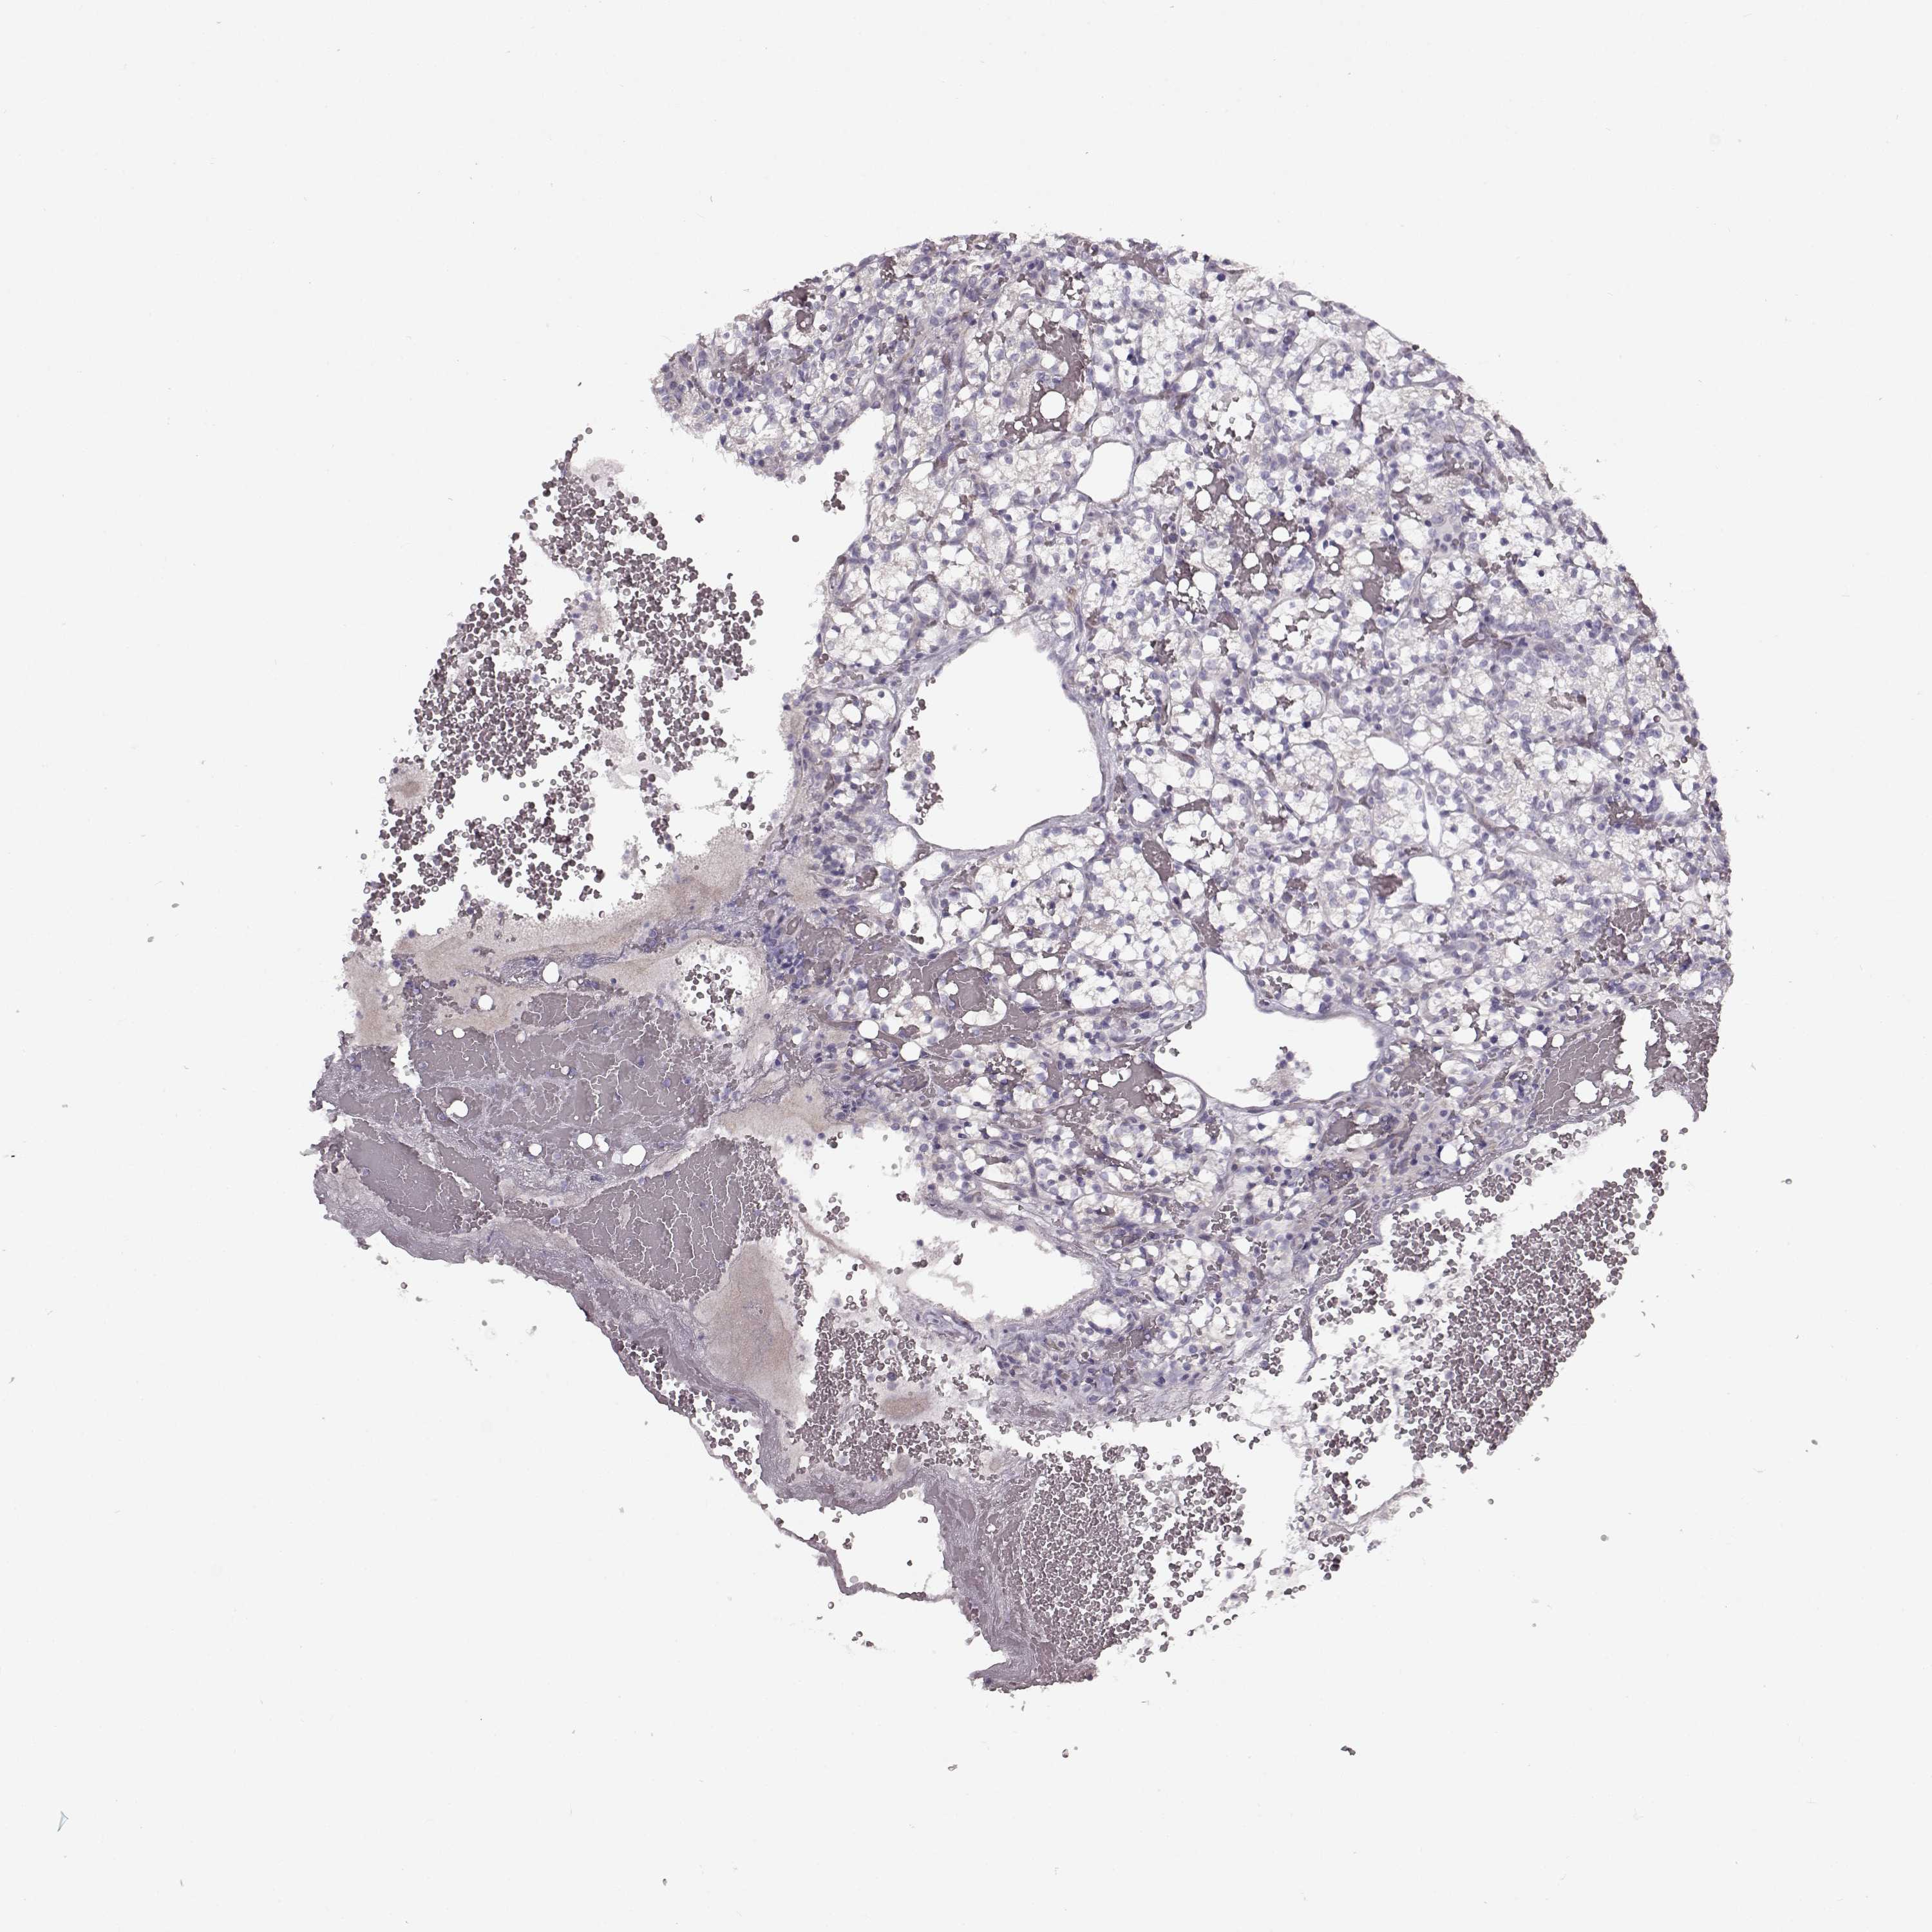

CANCER RENAL CANCER Show tissue menu

Kidney chromophobe

KIDNEY CHROMOPHOBE (TCGA) - Interactive survival scatter ploti

The Survival Scatter plot shows the clinical status (i.e. dead or alive) for all individuals in the patient cohort, based on the same data that underlies the corresponding Kaplan-Meier plots. Patients that are alive at last time for follow-up are shown in blue and patients who have died during the study are shown in red.

The x-axis shows the expression levels (FPKM) of the investigated gene in the tumor tissue at the time of diagnosis. The y-axis shows the follow-up time after diagnosis (years). Both axes are complimented with kernel density curves demonstrating the data density over the axes. The top density plot shows the expression levels (FPKM) distribution among dead (red) and alive patients (blue). The right density plot shows the data density of the survived years of dead patients with high and low expression levels respectively, stratified using the cutoff indicated by the vertical dashed line through the Survival Scatter plot. This cutoff is automatically defined based on the FPKM cutoff that minimizes the p-score. The cutoff can be changed by dragging the vertical line or by entering a cutoff value in the square labeled "Current cut-off".

Under the Survival Scatter plot the p-score landscape (black curve; left axis) is shown together with dead median separation (red curve; right axis). Dead median separation is the difference in median mRNA expression between patients who have died with high and low expression, respectively. It is calculated as follows: median FPKM expression of dead patients with high expression - median FPKM expression of dead patients with low expression. This is intended to aid the user in visually exploring custom cutoffs and the associated p-scores and dead median separation.

Individual patient data is displayed and can be filtered by clicking on one or more of the category buttons on the top of the page. Categories describing expression level and patient information include: high, low, alive, dead, female, male and tumor stages. The scale of the x-axis can be toggled between linear and log-scale by clicking on the "x log" button. Mouse-over function shows TCGA ID, patient information and mRNA expression (FPKM) for each patient.

& Survival analysisi

Kaplan-Meier plots summarize results from analysis of correlation between mRNA expression level and patient survival. Patients were divided based on level of expression into one of the two groups "low" (under cut off) or "high" (over cut off). X-axis shows time for survival (years) and y-axis shows the probability of survival, where 1.0 corresponds to 100 percent.

MAP6D1 is not prognostic in Kidney Chromophobe (TCGA)